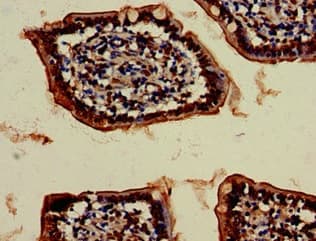

Rabbit Polyclonal VPS4B/MIG1 antibody. Suitable for WB, IHC-P, ICC/IF and reacts with Mouse, Human samples. Cited in 2 publications. Immunogen corresponding to Recombinant Fragment Protein within Human VPS4B aa 1-150.

Applications ICC/IF, IHC-P, WB

Species Reactivity Human, Mouse